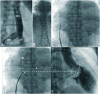

Figure 1

(A) Frontal-view venogram, obtained with contrast medium injected in RIV, through Mullins sheath, showing anomalous IVC course, with RIV drainage into IVC at an acute angle. (B) Fluoroscopic frontal composite view showing guide wire and needle assembly, inserted through LIV to superior vena cava. (C) Frontal view showing transseptal assembly set in right atrium. (D) Tip of dilator catheter/needle (white arrow) at optimal puncture site, namely crossing site of vertical M line and horizontal C line; M line indicates vertical line, intersecting mid-point of horizontal AL line. Point A indicates tip of pigtail catheter in contact with non-coronary sinus of Valsalva) and Point L, left atrial lateral silhouette (white dotted line); (E) 30° right anterior oblique view, showing horizontal line crossing center of mitral annulus (white dotted line). IVC, inferior vena cava; LIV, left iliac vein; RIV, right iliac vein (Refer to text and reference 2 for detail).